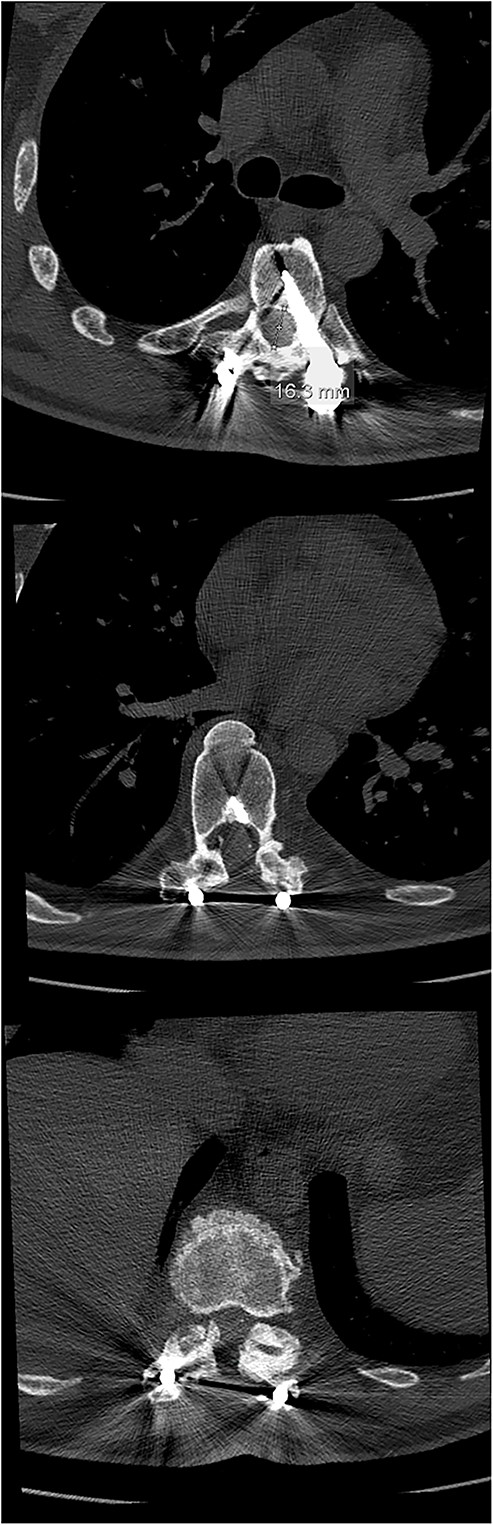

The initial CT scan (axial views), showing the width of the spinal canal at Th6 (above), Th9 (middle) and Th11 (below).